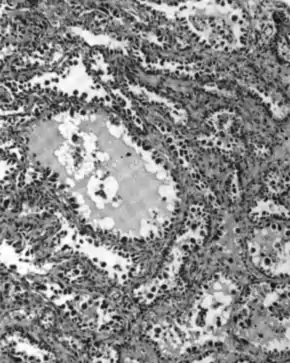

Micrograph of a mucinous ovarian carcinoma stained by H&E

Mucinous adenocarcinoma

Mucinous adenocarcinomas make up 5–10% of epithelial ovarian cancers. Histologically, they are similar to intestinal or cervical adenocarcinomas and are often actually metastases of appendiceal or colon cancers. Advanced mucinous adenocarcinomas have a poor prognosis, generally worse than serous tumors, and are often resistant to platinum chemotherapy, though they are rare.[29]